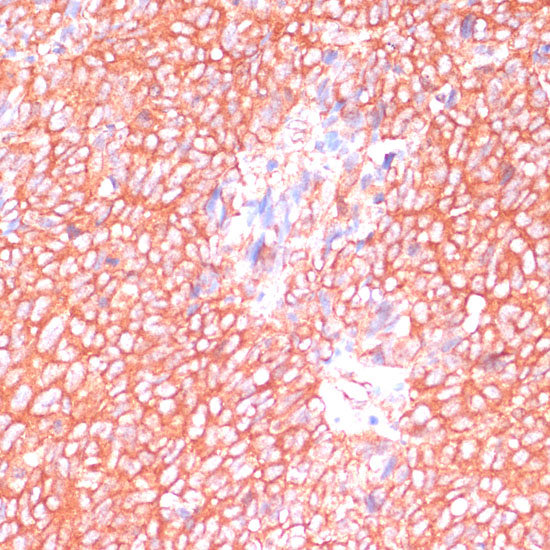

Immunohistochemistry of paraffin-embedded rat ovary using MOB4 at dilution of 1:100 (40x lens).

,

Immunohistochemistry of paraffin-embedded human oophoroma using MOB4 at dilution of 1:100 (40x lens).